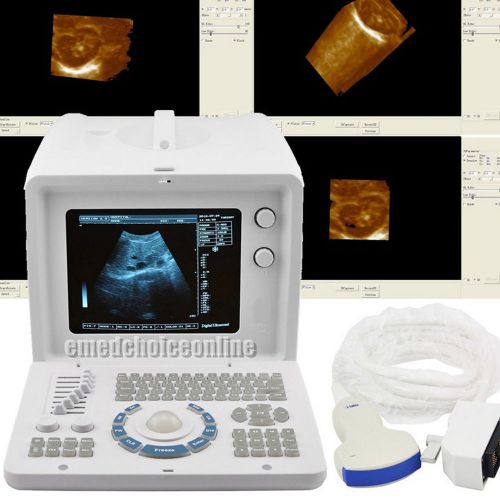

3D PC Plateform Based Full Digital Portable Ultrasound Scanner+3.5mhz convex pro

3D PC FULL digital Portable ultrasound scanner machine 3.5mhz Convex 3Y WARRANTY

Internal 3D 3.5mhz convex+6.5mh Transvaginal Portable Ultrasound Scanner machine

Internal 3D 3.5mhz convex probe Portable Ultrasound Scanner machine warranty

FDA Portable Digital Ultrasound Scanner CONVEX PROBE 3D software optional linear

CE FDA Full Digital Portable Ultrasound Scanner+Transvaginal Probe +3D Software

Portable Ultrasound Scanner Sysytem Machine +7.5MHZ Linear probe+WARRANTY

CE FDA Ultrasound Scanner Machine +Convex Probe +Free 3D Software + 2ys warranty